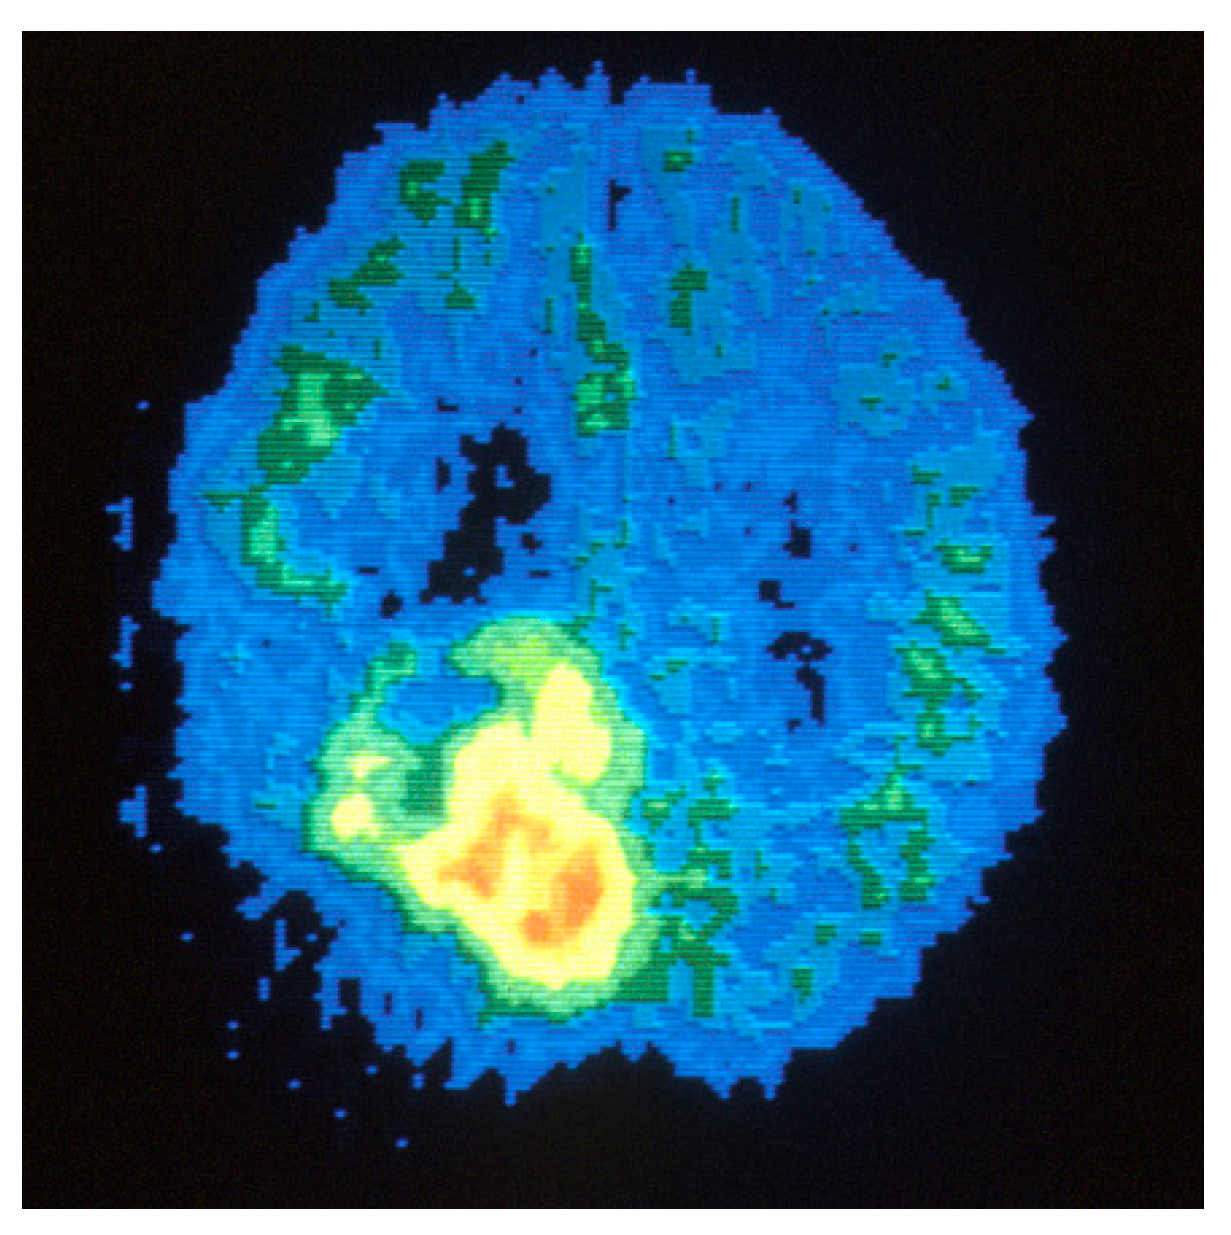

3.3. PET